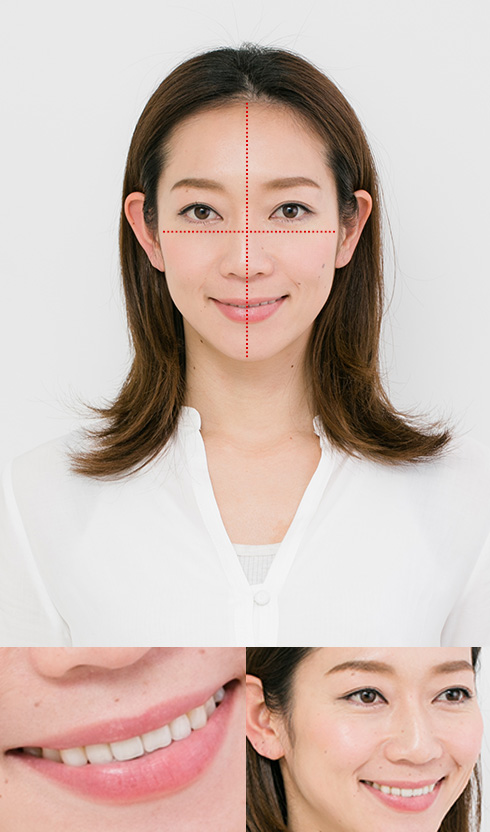

美しい歯並びを創る3つの黄金バランス

「顔」「あご」「歯」を正しく翻訳する

一人ひとりの症状を診断し、「顔」・「顎」・「歯」にクローズアップしながらそれぞれのパーツバランスを診て、丁寧に1mmずつ歯を動かしていきます。正常な咬み合わせの習慣が定着できるように治療を進めます。

患者様のお顔の“翻訳”から始まる総合的な矯正分析を実践

ライフ歯科・矯正歯科では、歪みの原因となる箇所を多方面の精密検査で診断します。顎の関節運動から、顎骨格の形状、歯並びの状態などを頭部X線や歯列模型採取、咬合器などで、詳細な精密検査で分析し、最適な治療計画、治療法で行います。